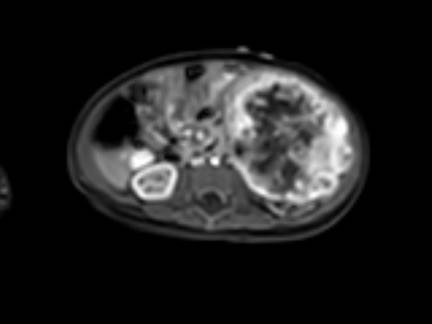

Hình ảnh MRI của một bé gái chín tháng tuổi có khối u ở bụng trái. MRI cho thấy khối u tuyến thượng thận trái, một phần đặc, một phần nang. Có nhiều di căn gan.

Khối u đã được sinh thiết. Có tình trạng chảy máu liên tục qua kim dẫn đường. Vào cuối thủ thuật, hai nút bọt gelatin đã được đặt vào (các dải tăng âm (mũi tên)).